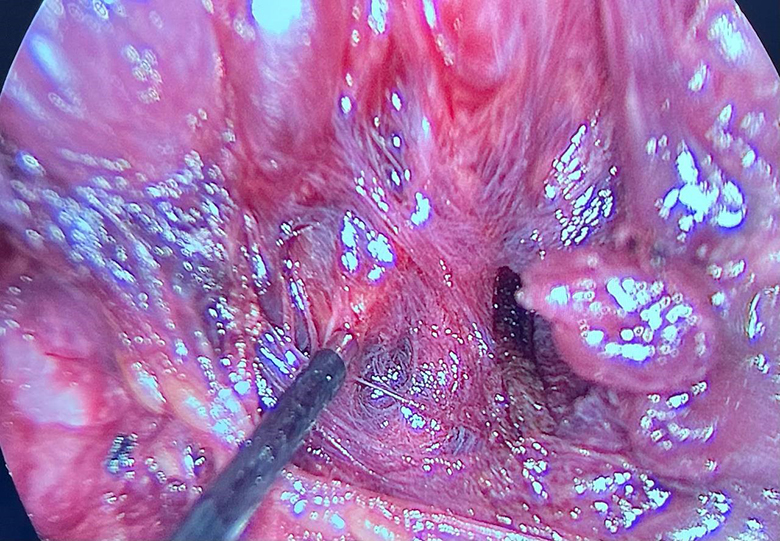

Операция видеоэндохирургическая гемитиреоидэктомия с истмусэктомией справа (удаление одной доли щитовидной железы и ее перешейка) у пациента 40 лет с доброкачественным образованием щитовидной железы проводилась эндоскопическим методом: эндоскопическая техника дает несравнимую с открытыми операциями возможность визуализации всех анатомических структур. В начале операции, приблизившись к нервам, мы проверили «замкнутость цепи»: если нерв отвечает на стимуляцию, на мониторе появляется сигнал, по его амплитуде оценивается степень его травматизации, что позволяет внести коррективы в ход хирургического вмешательства. Так определяют наличие или отсутствие проблем, НЕ связанных с данной операцией. На рис. 2 сигнал от возвратного гортанного нерва. Далее в процессе операции, как я уже отмечал выше, можно в любой момент контролировать сохранность функции нерва.

Визуализация возвратного гортанного нерва Стимуляция гортанного нерва

Стимуляция вагуса